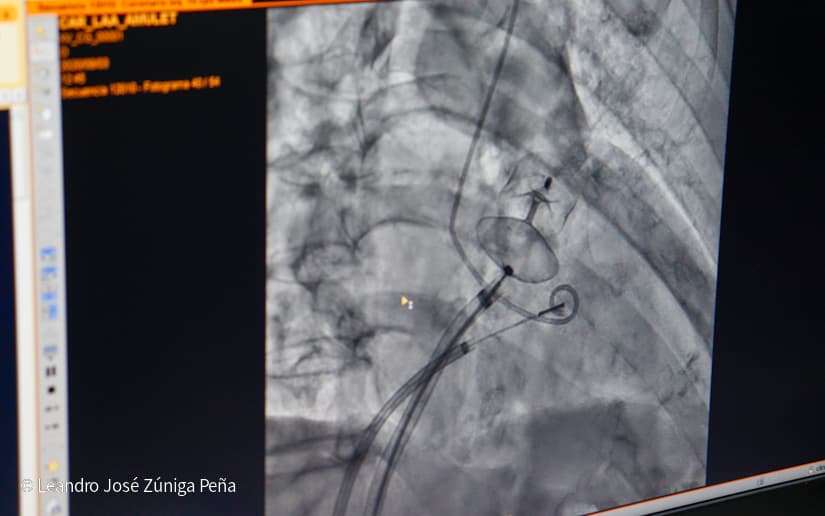

El doctor Álvaro Escalante, coordinador del área de Cardiología del Hospital Manolo Morales, indicó que este equipo permite tratar enfermedades coronarias o del corazón, arteriales periféricas, pacientes en hemodiálisis, oncológicos y con trastorno de las vías biliares.

Escalante explicó que este equipo emite rayos x de alta tecnología que permite ver el corazón y a la misma vez intervenir, de tal forma que se puede llegar a las arterias de pacientes que casi tienen un infarto, igualmente arterias obstruidas de los brazos y miembros evitando que se les amputen, así como en pacientes oncológicos la obstrucción de arterias que estén alimentando los tumores y así llevar quimioterapias, y abrir vías biliares que tengan obstrucción tumoral de la misma.

También se puede tratar las arritmias en todos aquellos pacientes que tienen palpitaciones o desmayan por x o y motivo y con este equipo se determina la causa y se tratan mediante estudio electrofisiológico y la ablación por radiofrecuencia, así como la implantación de marcapasos.